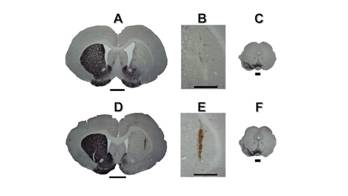

Histological analysis: The analysis with immunohistochemistry for T-H showed well-established immune labeling in the left striatum of the SiO2 group (see Figures 8A-B), and SiO2-DA group (see Figures 8D-E), and the left mesencephalon (8C and 8F) for all the lesioned rats. The right striatum and the right side of the mesencephalon showed a lack of immuno-labeling because of the loss of the nigrostriatal pathway with 6-OHDA. In the slices of the right striatum, there was no evidence of DAergic cell regeneration of the nigrostriatal pathway. The presence of reddish-brown particles is remarkable through the SiO2-DA reservoir pathway in the left striatum (see Figures 8D-E) in remarkable contrast to the SiO2 reservoir pathway (see Figures 8A-B) which was translucent. The reddish-brown particles in the SiO2-DA pathway suggest the presence of oxidized molecules, probably DA, which could be oxidized during the brain-fixing process. (Figure 8)

Figure 8 Immunochemistry to T-H in coronal slices of rat’s brain (50 µm) at the level of the striatum and the mesencephalic region. A-B, Coronal slices of rat’s brain at the striatum level with SiO2 reservoir. D-E, Coronal slices of rat’s brain with SiO2-DA reservoir. Scale bar 2 mm. C and F mesencephalic coronal slices with immunochemistry to T-H, where is located the SNpc. B and D are higher magnifications of the areas where are localized the reservoirs. Is noticeable that the pathway of the reservoir with DA has a reddish-brown color, suggesting the presence of oxidizable DA. The slices with immunochemistry to T-H at the striatum and mesencephalic levels (C-E and H-J) clearly show the absence of immune-labeling at the right side of the slices, suggesting the lack of the DAergic cells of the nigrostriatal pathway at that side.